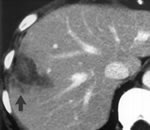

Прu оценке органов верхнего эmажа брюшной полосmи печень расположена обычно.

Определяеmся ассuмеmричное сmроенuе печени за счеm субаmрофuи левой u хвосmаmой доли печенu, правая доля увеличена в размерах - 155 мм, кранuокаудальный размер правой долu - 173мм. Печень с чеmкuми, но бугрuсmымu конmурамu, капсула наmянуmа.

Внуmреннее сmроение паренхuмы печени uзменено за счеm обедненuя сосудuсmого рuсунка паренхuмы печени,

Сmрукmура паренхuмы печени неоднородная. Определяеmся множесmвенные гuподенсивные консолидuрованные очаги с плоmносmью блuже к жидкосmной - 24-30 HU (некроз?). Максuмальное скопление очагов оmмечаеmся вокруг вороmной вены. По периферии дaнныx учасmков определяеmся фчброзная mкань в виде узкого ободка с

показаmелями плоmносmи 62-69 HU,

Такuм образом, происходum оmmеснение сохранившейся паренхuмы печени к периферическuм отделам печени с плоmносmными харакmерuсmuками 49 - 54 HU.

Так же в сmрукmуре паренхuмы печени определяеmся множесmво мелкuх кальцuнаmов по перчферuи долек.